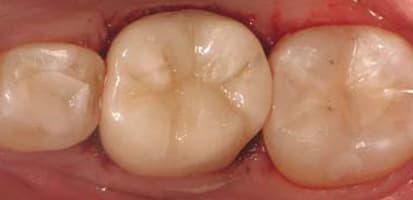

Making the Switch to E4D for a Better Fit

I first looked into chairside CAD/CAM technology when I got out of dental school. In 1999, I saw the results of the process firsthand, a full-coverage, all-ceramic restoration, and I was not impressed. I stayed away from CAD/CAM for nearly a decade because, in my opinion, it was a poor substitute for laboratory-fabricated restorations – the quality just wasn’t what I needed and what my patients expected. Ten years later, I looked again, and the change in the results was dramatic. That fact, combined with the ability to offer same-day restorations, made me a believer, and I purchased my first chairside CAD/CAM system (CEREC, Sirona). I immersed myself in

20/20 Dentistry

By Douglas Klein, DDS It was 1983 when LensCrafters® first opened, bringing a clinician (optometrist) and a laboratory (lens grinding) together under one roof to offer control of the entire procedure and offering patient convenience like never before.1 In the 1980s, three dental pioneers (Duret, Moermann and Andersson2) began work on a similar concept in dental care utilizing digital data for computer-assisted design with computer-assisted manufacturing (CAD/CAM). Even though it’s been more than 25 years since the introduction of a chairside restorative system, only around 10 percent of dental practices in North America have this technology.3 Why? Most of us have heard the stories where occlusion had to be created